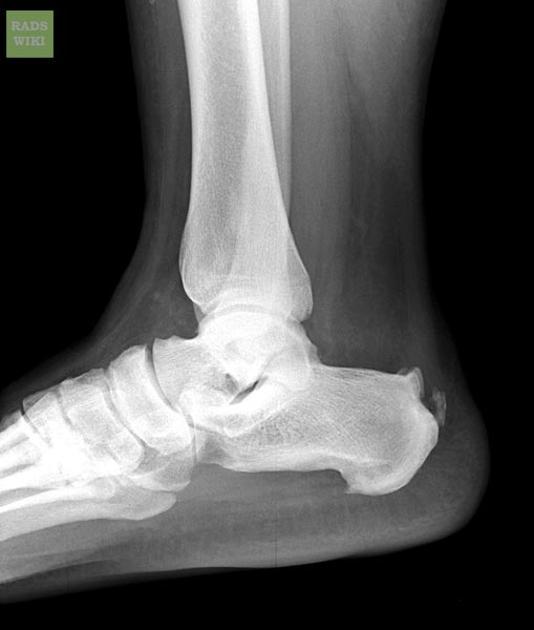

Haglund deformity

”pumps bump”

postero-superior calcaneus from high heels usually

how do we know if this fracture is intraarticular in extension?

Boehler angle is reduced (normally 20-40, here is 10)

CT can confirm (sanders classification)